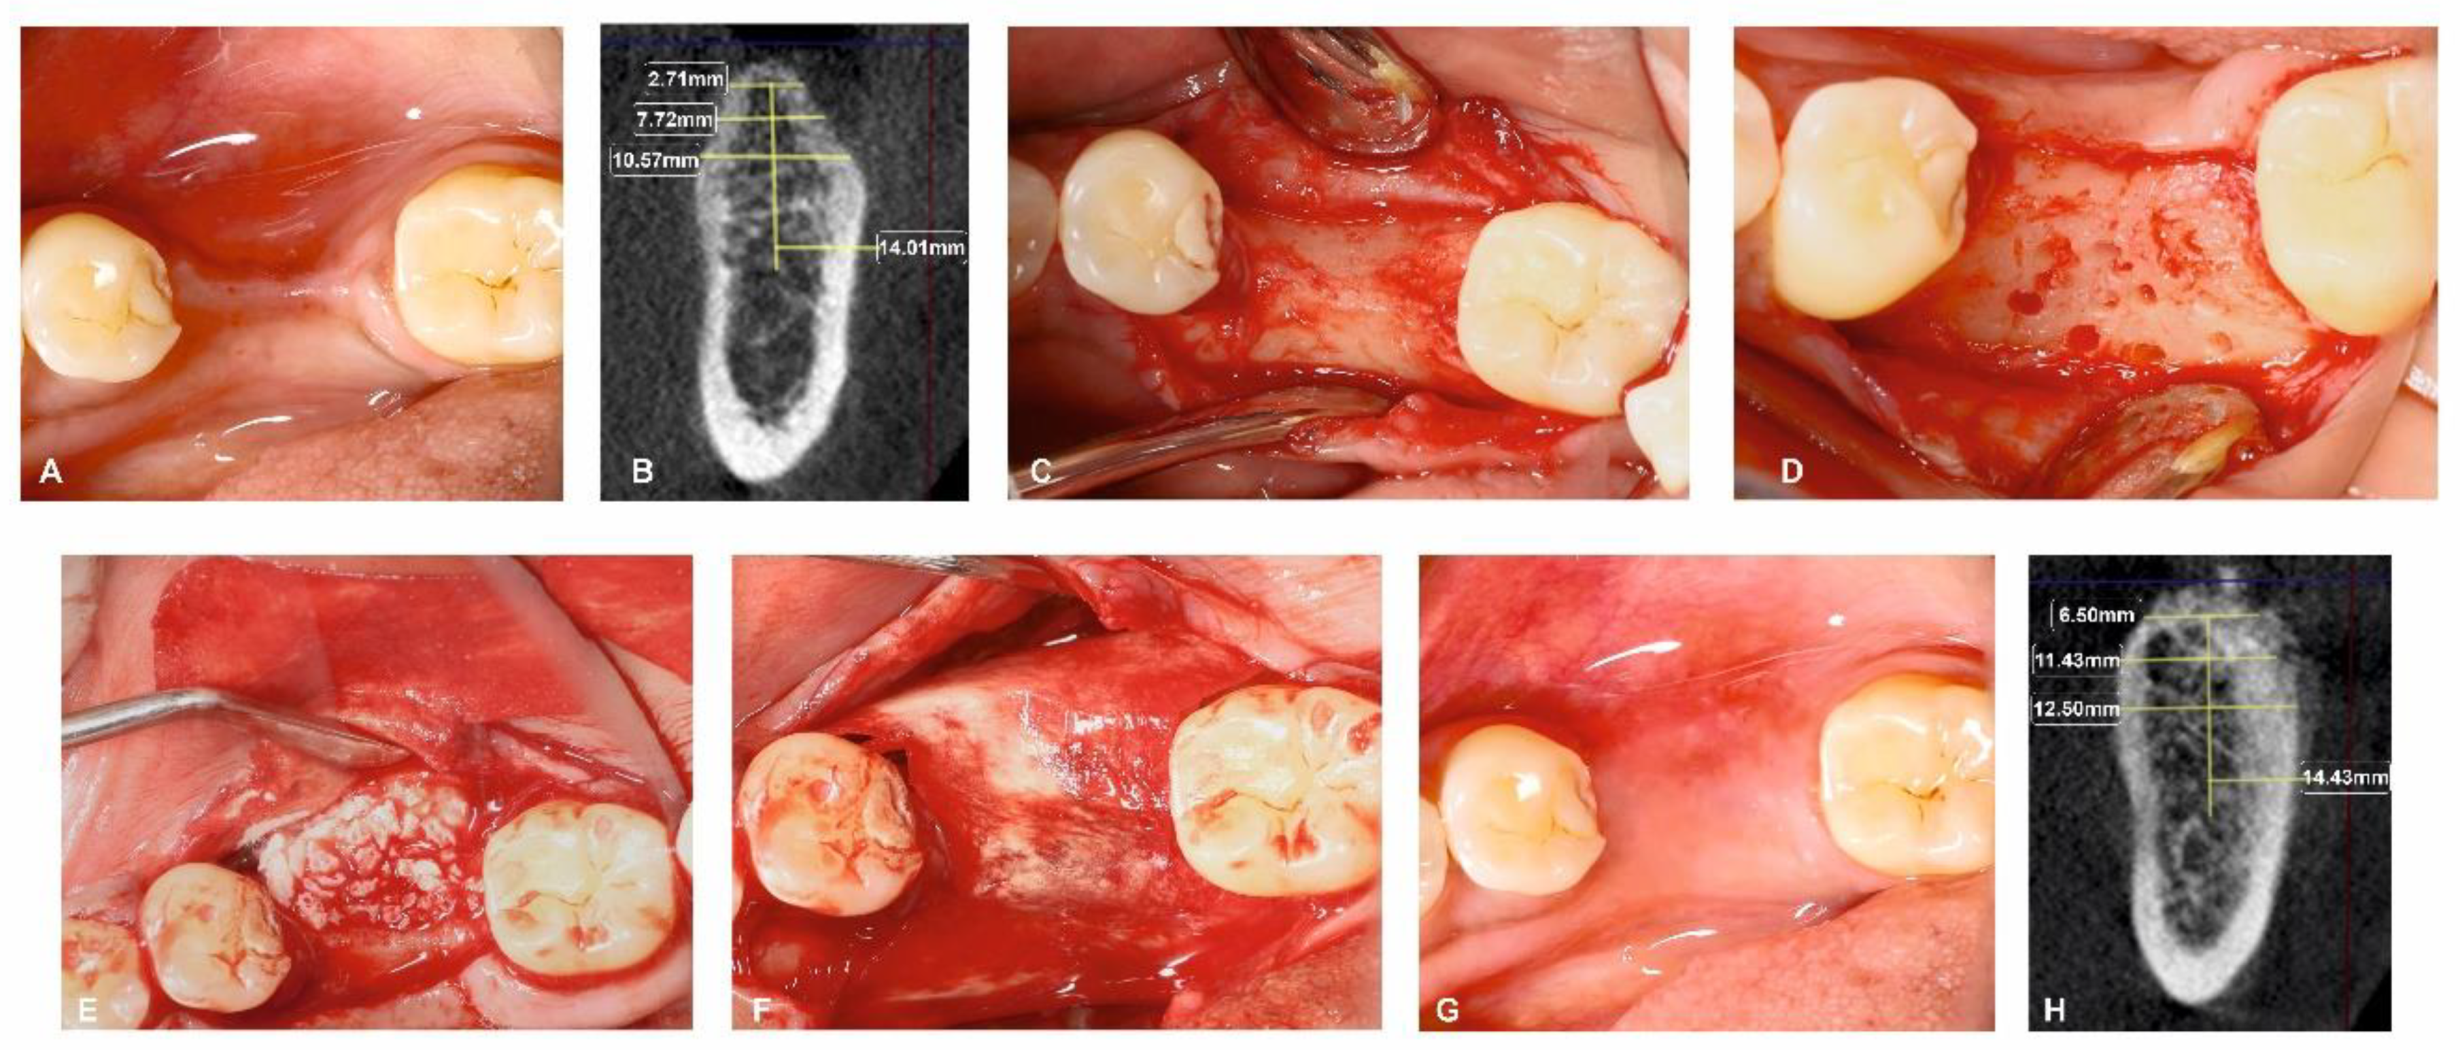

Figure 2.

Surgical management of horizontal ridge defect (group-I). (A) Preoperative horizontal ridge deficient site; (B) HRW and VBH measurements assessed at crest, at 3 mm, and at 6 mm in baseline; (C) Flap elevation; (D) Decortications performed in the surgical site; (E) Sticky bone placement; (F) Collagen membrane adapted over the sticky bone; (G) 6-month follow-up; (H) HRW and VBH measurement assessed at crest, at 3 mm, and at 6 mm at 6 months.

All surgical procedures were carried out by a single, trained periodontal surgeon (H.P). For both Group I and Group II, local anaesthesia was administered using 2% lignocaine with adrenaline. After performing a mid-crestal incision through the keratinized gingiva, a full-thickness flap was raised on the buccal and lingual side. To enable osteoprogenitor cell migration, multiple neo-angiogenetic cortical holes were made in the recipient bone bed. A total of 10 mL of venous blood obtained from the antecubital vein in non-coated plastic vacutainers was immediately spun in a centrifuge at a pre-programmed spin to obtain i-PRF (700 rpm for 3 min with 60 g force) (Dentifuge LC-100). The prepared i-PRF was mixed with ABBM (Bio-OSSTM, Geistlich®, Zurich, Switzerland) (Figure 1); polymerisation takes approximately 5–10 min, resulting in sticky bone formation [22,23,24]. In Group I, sticky bone was adapted and moulded over the defect to the level of the adjacent neighbouring buccal bony contour. A bi-layered cross-linked collagen membrane (Cologide™, Cologenesis Healthcare Pvt Limited) of adequate size was chosen and cut to fit the defect size, and it was employed to cover the bone grafts with a 2 mm overlap buccally (Figure 2A–H) and on the lingual side the membrane was tucked inside the lingual flap; in Group-II, the same protocol as Group-I was followed, with the placement of the prepared sticky bone without the collagen membrane (Figure 3A–H). Tension-free primary closure was achieved with simple, interrupted (3-0 Vicryl, Ethicon) sutures in both groups. Six months after the augmentation, cone beam-computed tomographic (CBCT) images were taken.